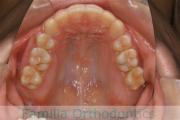

全体的なでこぼこを治したいということで来院されました。上顎は右は4,左と下顎両側は5番を抜歯して、マルチブラケット法にて治療を行いました。2年強、25回程度の通院をしていただきました。

非常に強いでこぼこですので、後戻りのリスクは高めであると思われます。